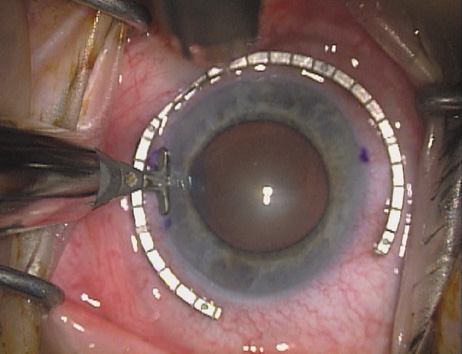

ways. Our preferred method makes use of a modified Fine-Thornton fixation

ring (Nichamin Fixation Ring and Gauge; Mastel Precision, Storz, Rhein

Medical). This instrument serves to fixate and position

the globe in order to optimize incision placement, as well as to delineate

the extent of arc to be incised. One visually extrapolates from

the limbus to marks on the surface of the ring. Each incremental mark

is 10 degrees apart, and bold hash marks (180 degrees) opposite

to each other serve to align and center the incision over the steep

meridian. This approach obviates the need to ink and physically mark

the cornea. If one desires, particularly when first gaining experience

with LRIs, a two-cut RK marker may be used to place ink marks upon the

cornea to show the exact extent of arc that is to be incised, in conjunction

with the fixation ring/gauge (Fig. 4). Alternatively, various press-on markers are available, such as

markers, rings, and blades for performing LRIs.  Fig. 4. The Nichamin Fixation Ring and Gauge serves to both fixate the globe and

delineate the extent of arc to be incised; a two-cut radial marker may

be used to mark the extent of arc to be incised, and the Mastel Nichamin

Force AK Diamond Blade with preset depth of 600 microns. Fig. 4. The Nichamin Fixation Ring and Gauge serves to both fixate the globe and

delineate the extent of arc to be incised; a two-cut radial marker may

be used to mark the extent of arc to be incised, and the Mastel Nichamin

Force AK Diamond Blade with preset depth of 600 microns.